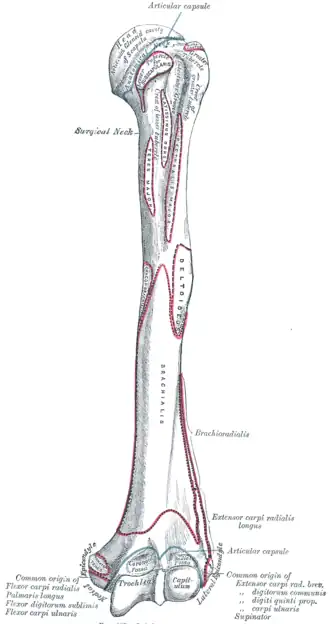

Left humerus. Anterior view. (Radial fossa visible at bottom right.) | |

The radial fossa is a slight depression found on the humerus above the front part of the capitulum. It receives the anterior border of the head of the radius when the forearm is flexed.

The joint capsule of the elbow attaches to the humerus just proximal to the radial fossa.[1][2]